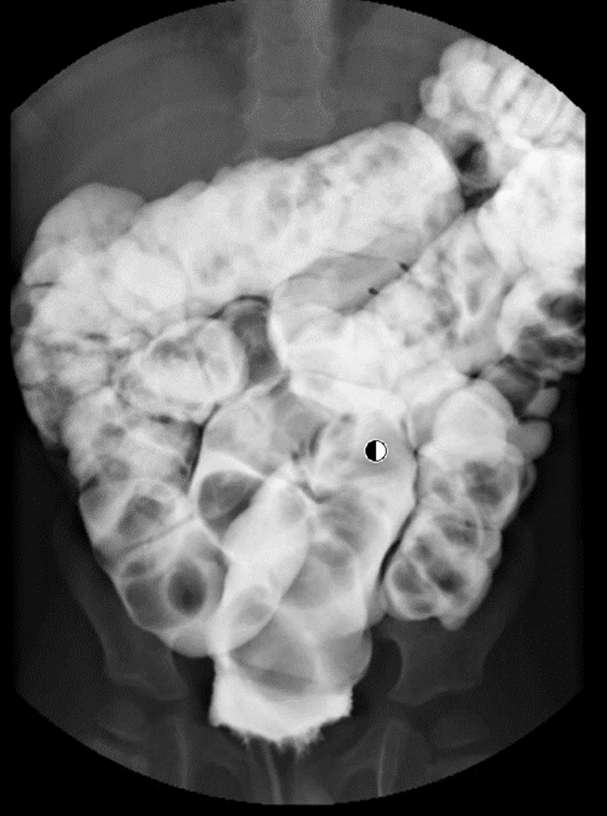

- Contrast enema (Figure 1): useful to study the anatomy/ shape of the colon; useful to exclude Hirschsprung disease; can be both diagnostic and therapeutic (for medical disimpaction with gastrograffin enema)

Figure 1: Contrast enema in a 2 year-old boy shows faecal impaction (black and round filling defects ) with very redundant sigmoid and transverse colon